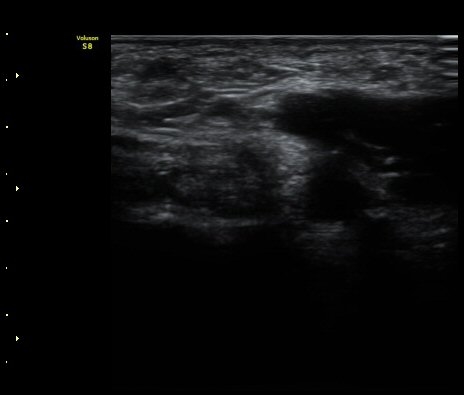

ÃÊÀ½ÆÄ °Ë»ç

¤º